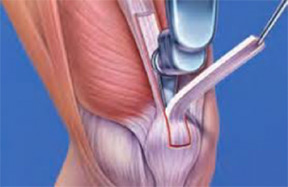

Las técnicas quirúrgicas son artroscópicas (visualización de una articulación), empleando para la reconstrucción del ligamento cruzado anterior injertos autólogos (del mismo paciente) de tendones isquiotibiales, tendón rotuliano o tendón cuadricipital, como aloinjertos (provenientes de donantes).

Isquiotibiales

Tendón rotuliano

Tendón del cuádriceps

En el mismo acto quirúrgico, se deben reparar lesiones secundarias como cartílago y menisco. Las lesiones meniscales deben intentar suturarse para preservar la mayor cantidad del mismo.